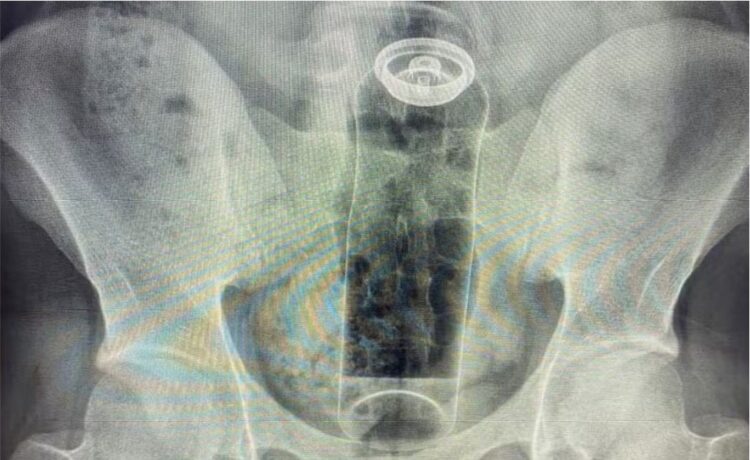

O cirurgião Daniel Brosco relatou, em suas redes sociais, o atendimento a um jovem de 19 anos que precisou ser internado após introduzir um desodorante no ânus durante uma brincadeira sexual. Segundo o médico, o objeto acabou sendo “puxado” para o reto e não pôde ser retirado em casa, exigindo intervenção hospitalar.

De acordo com Brosco, situações como essa têm se tornado cada vez mais frequentes. Nos últimos meses, ele afirma ter atendido pacientes que precisaram retirar do reto objetos como batatas, partes de cadeira, garrafas de vidro e até plugs anais utilizados de forma inadequada. O risco, explica, está ligado aos movimentos naturais do intestino, chamados de peristálticos, que podem “sugar” rapidamente qualquer objeto introduzido.